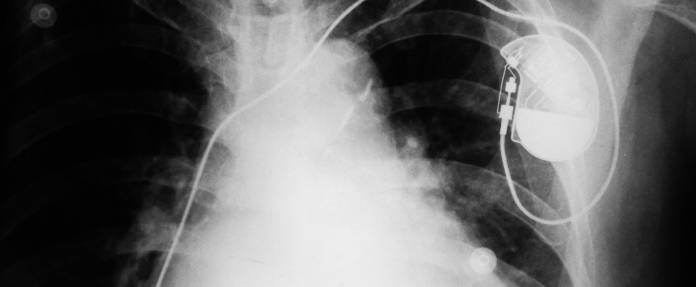

Das Implantieren eines Herzschrittmachers ist heute mit ausschließlich örtlicher Betäubung möglich. Der Eingriff dauert etwa eine Stunde. Je nach Art des Herzschrittmachers werden über die Venen Sonden mit Elektroden zum Herzmuskel geführt und dort verankert, wo der Impuls wirken soll. Dies können die Wand der Herzkammer oder der Herzvorhof sein. Die Position der Sonden wird mittels einer Röntgenaufnahme überprüft und ihre Funktion gemessen.

Anschließend findet das Aggregat des Herzschrittmachers seinen Platz in einer Gewebetasche unterhalb des Schlüsselbeins. Das Gerät als solches ist ein winziger Computer mit einer Lithiumbatterie. Die Sonden werden nun angeschlossen.